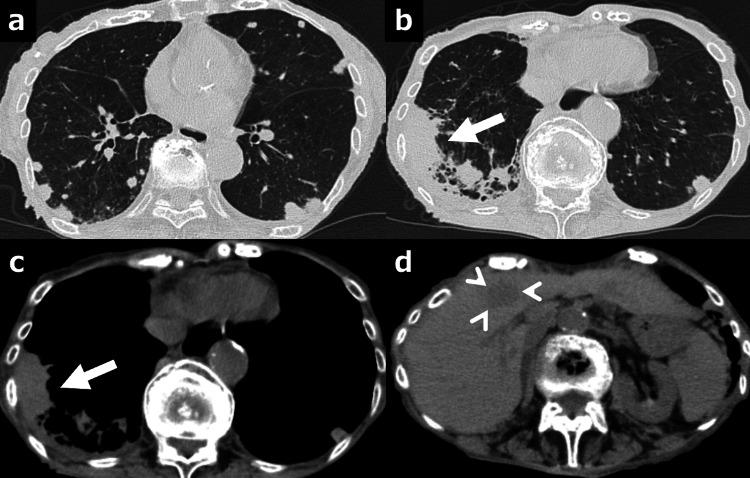

Diffuse large B-cell lymphoma (DLBCL) is a high-grade malignancy. We present a case of a 97-year-old female with gastric cancer and DLBCL in whom remission with rituximab-containing minimum chemotherapy was sustained for 10 years. As she had severe adverse effects, she refused further treatments for both tumors. Ten years after the initial treatment, examinations showed several tumors in the lungs, the right pleura, and the liver, as well as advanced gastric cancer. She eventually passed away, and the autopsy revealed that multiple tumors were not lymphoma, but adenocarcinoma. This case report is a valuable addition to the literature as it analyzes whether rituximab-containing minimum chemotherapy is effective for elderly DLBCL and delineates the natural history of gastric cancer.

弥漫性大B细胞淋巴瘤(DLBCL)是一种高度恶性肿瘤。我们报告一例97岁女性患者,患有胃癌和DLBCL,接受含利妥昔单抗的最小化化疗后缓解持续了10年。由于她出现了严重的不良反应,拒绝了针对两种肿瘤的进一步治疗。初始治疗10年后,检查发现肺部、右侧胸膜和肝脏有多处肿瘤,同时患有进展期胃癌。她最终去世,尸检显示多处肿瘤并非淋巴瘤,而是腺癌。本病例报告为文献增添了有价值的内容,因为它分析了含利妥昔单抗的最小化化疗对老年DLBCL是否有效,并描述了胃癌的自然病程。